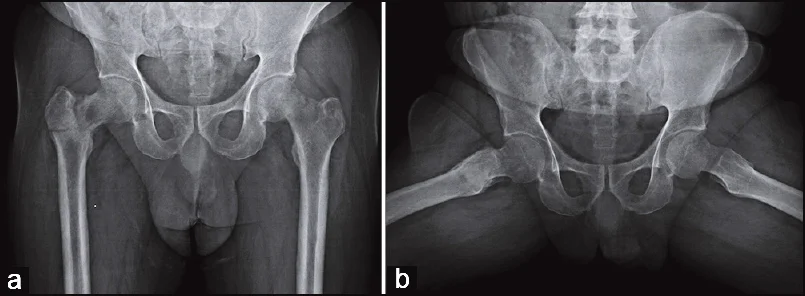

Case 6: 2-year-old with Fever, Vomiting, Pain L Hip

Patient Profile: 2-year-old with fever, vomiting, pain L hip, limited ROM

Key Features:

- Localized osteopenic lesion upper metaphysis L femur

- Reaching epiphyseal plate

Differential Diagnosis: Osteomyelitis, Septic arthritis

Further Investigation:

- CBC, Diff. WBC, CRP, ESR

- Ultrasound

- MRI

Ultrasound Findings: U/S: large hip effusion with echogenic content (Pus)

MRI Findings: MRI: hyperintense T2, Oedema, Fluid collection outside bone, Effusion in hip joint